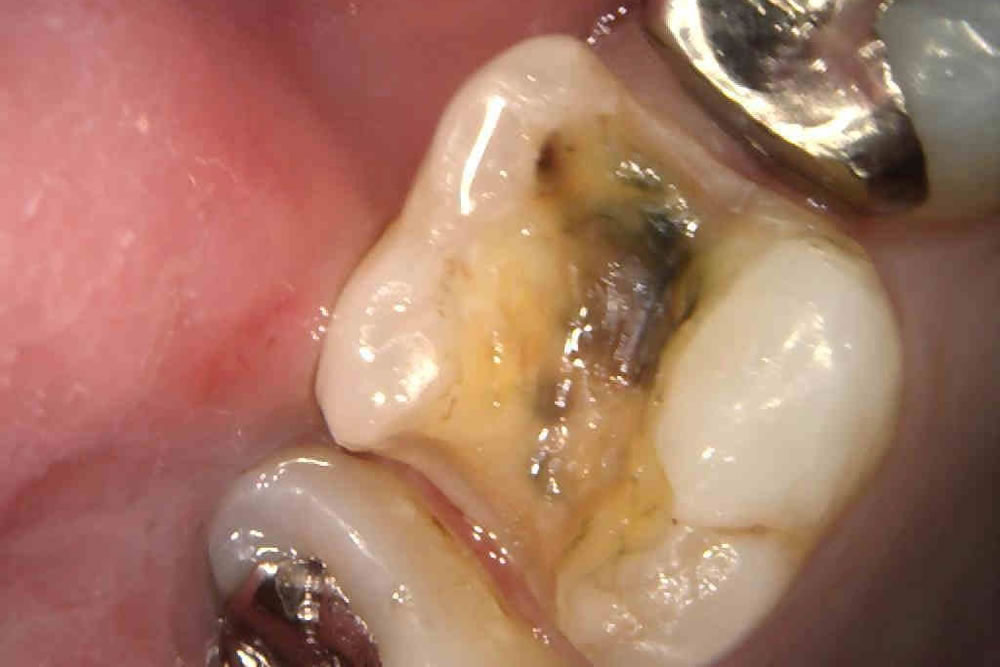

二次むし歯を治療後にハイブリッドインレーで修復した症例

年齢

20代

性別

男性

症例を見る